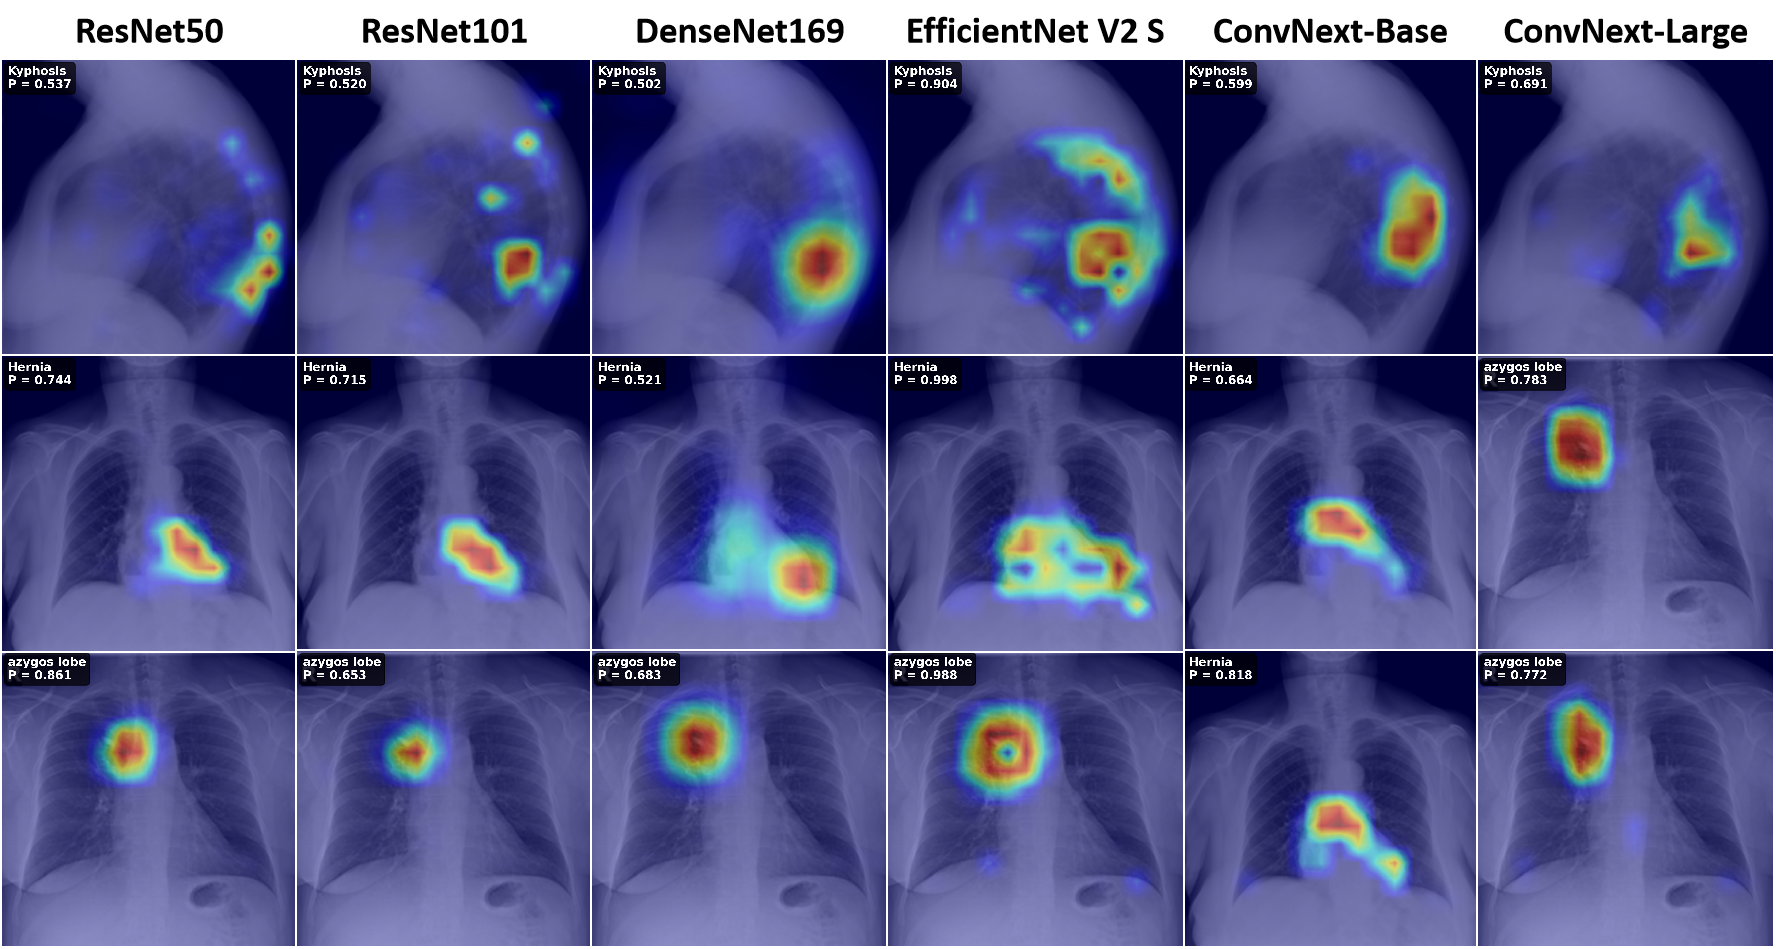

Given a chest X-ray image, the goal is to predict a binary label vector for 30 disease classes. This multi-label setting allows multiple findings to co-occur in a single image. We investigated several approaches in the perspective of loss functions, backbone architectures and post-training techniques to address the extreme class imbalance and multi-label nature of the task. We experimented with Label-Distribution-Aware Margin Loss combined with Deferred Re-Weighting (LDAM-DRW), Asymmetric Loss, and standard Binary Cross-Entropy (BCE) as baselines. For backbone architectures, we evaluated ResNet-50/101, DenseNet-121/169, EfficientFormerV2-S and ConvNeXt-Base/Large. Post-training strategies included classifier re-training (cRT), test-time augmentation (TTA), probability calibration (Prob Calib.) and ensembling.

We experiment with ResNet-50 model trained with different loss functions and post-training strategies to demonstrate the impact of each component on performance. We see that change of loss function from BCE to LDAM+DRW helps in 30.5% increase in MAP. And adding the cRT post-training strategy further improves the performance by 1.4% in MAP. While the cRT and TTA combined imrpoves by 1.9% in MAP. We then finalize the LDAM+DRW loss function for further model experiments, where ResNet-101 models gives 0.4584 MAP, DenseNet-121 gives 0.3967 MAP, DenseNet-169 gives 0.3981 MAP, EfficientFormerV2-S gives 0.4869 MAP, ConvNeXt-Base gives 0.4855 MAP and ConvNext-Large gives the highest MAP of 0.5220. The cRT helps the ConvNext-Base model to increase it performance by 3.8%, and adding up the TTA furtherly increase it by 7.4%. While the cRT and probability calibration degrades the performance and even the ensemble of ConvNext-Large and EfficientFormer-V2 S model with cRT also gives lower performance, than the standard ConvNext-Large with LDAM+DRW.